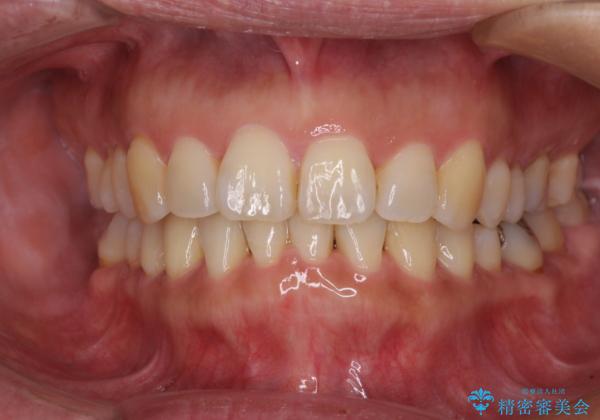

- 上下前歯の叢生を気にして来院された患者様です。

費用を抑え、期間もあまりかけずに治療をしたいとのことで、インビザライン・ライトを用いて矯正治療を行うこととしました。

インビザライン・ライトは、製作できるアライナーの枚数に制限があるため、移動可能な量に限りがあります。

一方で、半年から1年程度で治療を終えることができるため、軽度の歯列不正の患者様には大変お勧めです。